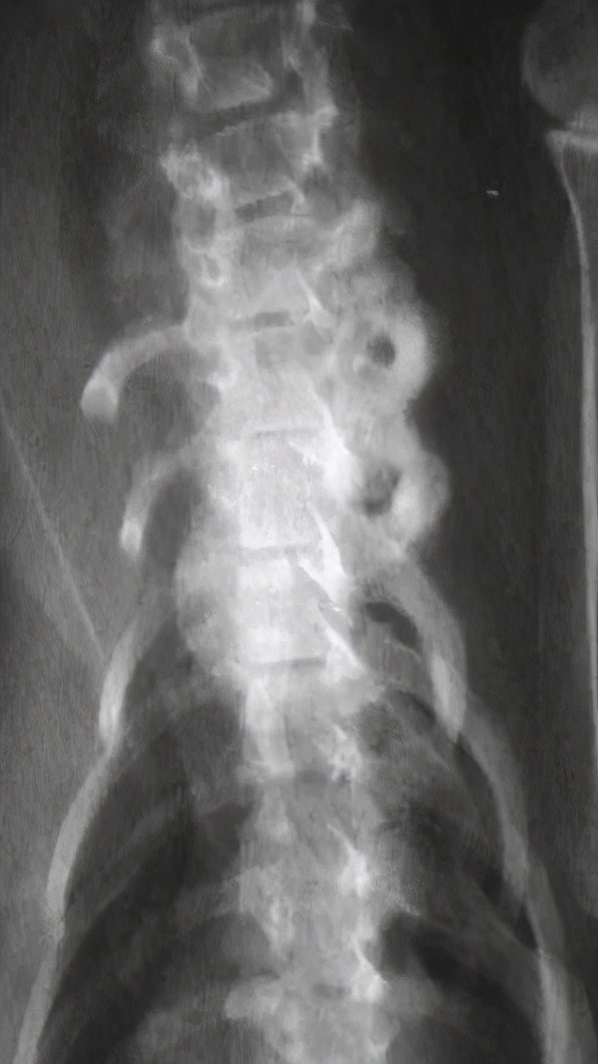

九岁 去势 公猫,长期以猪肝为主喂食自制食物。就诊时左前肢跛行,后出现霍纳氏综合征,两个月发展成瘫痪。

经病史检查,血液和影像学分析和以及血清维生素A浓度的测定,诊断为维生素A过量继发 神经丛压迫。

尾颈椎和颅胸椎腹侧新骨形成